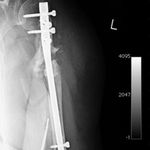

She was advised of the need to do some sort of stabilization which is necessary since the use of low-dose ultrasound has not helped in the healing process. She was unwilling to have any further operative intervention and sought further options. Eventually, she agreed to a fourth procedure of intra-medullary nail stabilization of the fracture and had this carried out in April 2011. An intramedullary nail was inserted in an antegrade manner and she has since gone on to heal the fracture site completely and has regained most of the function of the upper limb with no pain.